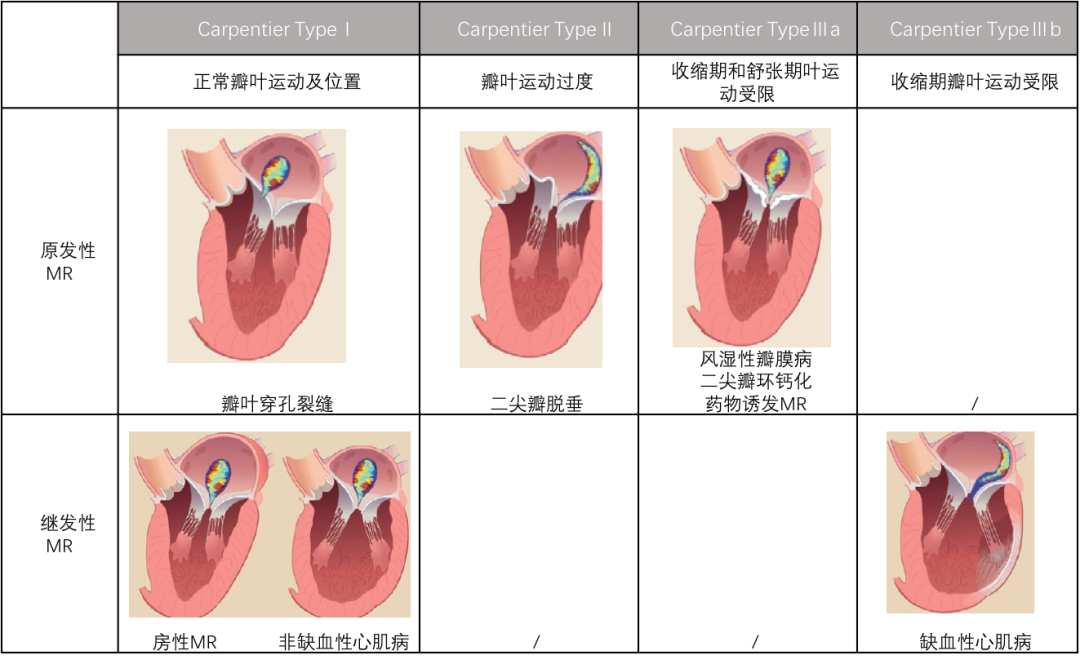

MitraClip于2003年首次植入,是目前使用最广泛的TMVr系统,迄今为止在全球范围内进行了超过150000次手术。MitraClip于2008年首次获得欧盟CE批准,2013年首次获得FDA批准,用于治疗原发性MR和手术风险高的患者,并于2019年3月批准用于治疗中重度或重度继发性MR,尽管存在治疗心力衰竭(GDMT)。受外科Alfieri缝合技术的启发,该导管缘-对-缘修复(TEER)系统最初设计用于通过使用一个或多个聚酯包覆的钴铬双臂夹子连接二尖瓣(MV)前叶和后叶的自由边缘来创建双孔(图5A)。MitraClip输送系统通过股静脉引入,带有一根可操作的24F引导导管(图5B),通过穿刺房间隔进入左心房(LA)。然后,夹子输送系统穿过导向鞘,夹子打开并定向,然后进入左心室(LV)。在经食道超声心动图(TEE)和透视引导下,导管被撤回,瓣叶自由边缘被抓住,从而MR减少(图6)。在释放之前,器械可以重新打开和重新定位,直到达到最佳效果。

ero为什么不显示经导管二尖瓣修复术:相关病理生理学、研究和治疗综述_https://www.jmylbn.com_新闻资讯_第7张

图5:MitraClip系统。(A)MitraClip器械。(B) MitraClip输送和引导系统。

ero为什么不显示经导管二尖瓣修复术:相关病理生理学、研究和治疗综述_https://www.jmylbn.com_新闻资讯_第8张

图6。(A,从左至右)透视和经食管超声心动图(TEE)图像显示经中隔穿刺后左心房(LA)内导管;

彩色多普勒经食管超声心动图(TEE)图像显示重度MR(B,从左到右)透视检查,彩色多普勒,以及三维经食管超声心动图(TEE)图像显示左心房(LA)中的片段。

(C,从左至右)透视和经食管超声心动图(TEE)图像显示,抓取瓣叶后,左心室(LV)中的夹子闭合;经食管超声心动图(TEE)图像显示二尖瓣平均压差为1毫米汞柱。

(D,从左到右)显示Clip释放的透视图像;彩色多普勒和三维经食管超声心动图(TEE)图像在手术结束时显示轻度MR。

LA:左心房;MR:二尖瓣返流;TEE:经食管超声心动图。